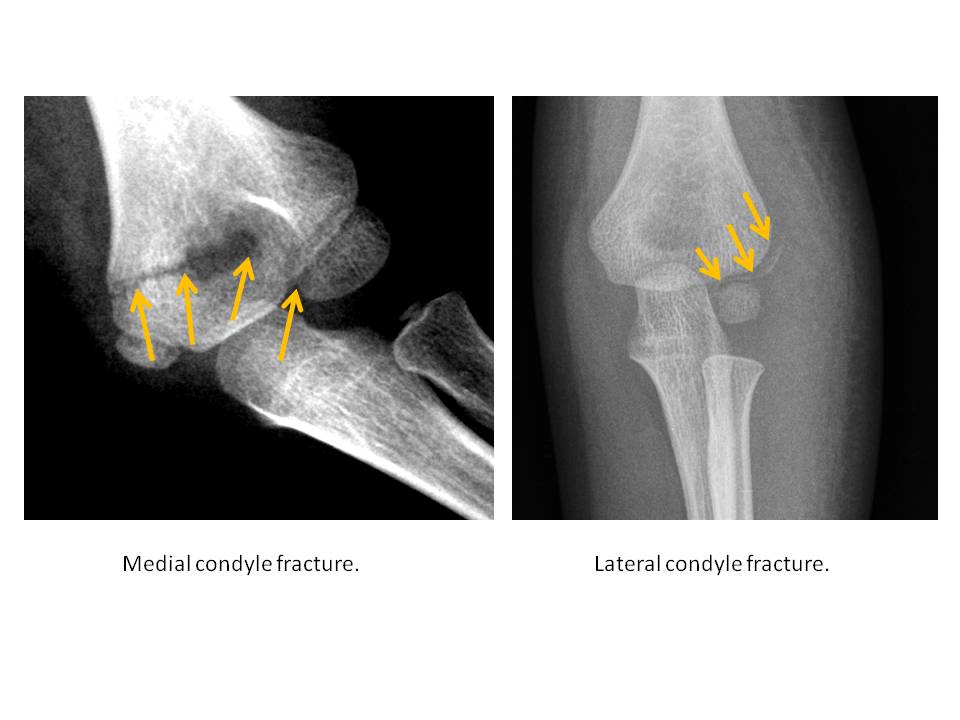

The medial or lateral humeral condyles are fractured. [Yes/No]